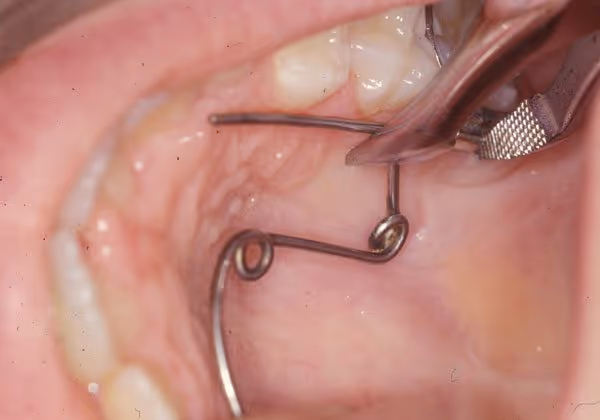

1- L’insertion du QH dans les tubes molaires: On commence habituellement par le côté le plus proche au praticien en utilisant une pince de Weinghart. L’autre coté sera pris avec précaution pour aligner le segment molaire avec l’entrée du tube (dans le sens du torque) et ensuite il sera insérer à fond avec la même pince.

2- Au premier RDV les bras du QH activé, seront orientés vers le centre, d’une façon symétrique ou asymétrique en fonction de la rotation des molaires. Cette position permet au QH de corriger la mauvaise rotation des molaires en premier.

3- Dans le plan vertical (occluso-palatin) il faut régler les bras en les mettant le plus proche possible au niveau des collets des dents latérales. Plus le bras est proche de la gencive papillaire marginale, plus il est proche du centre de résistance de la dent et moins il y aura de mouvement parasite de version.